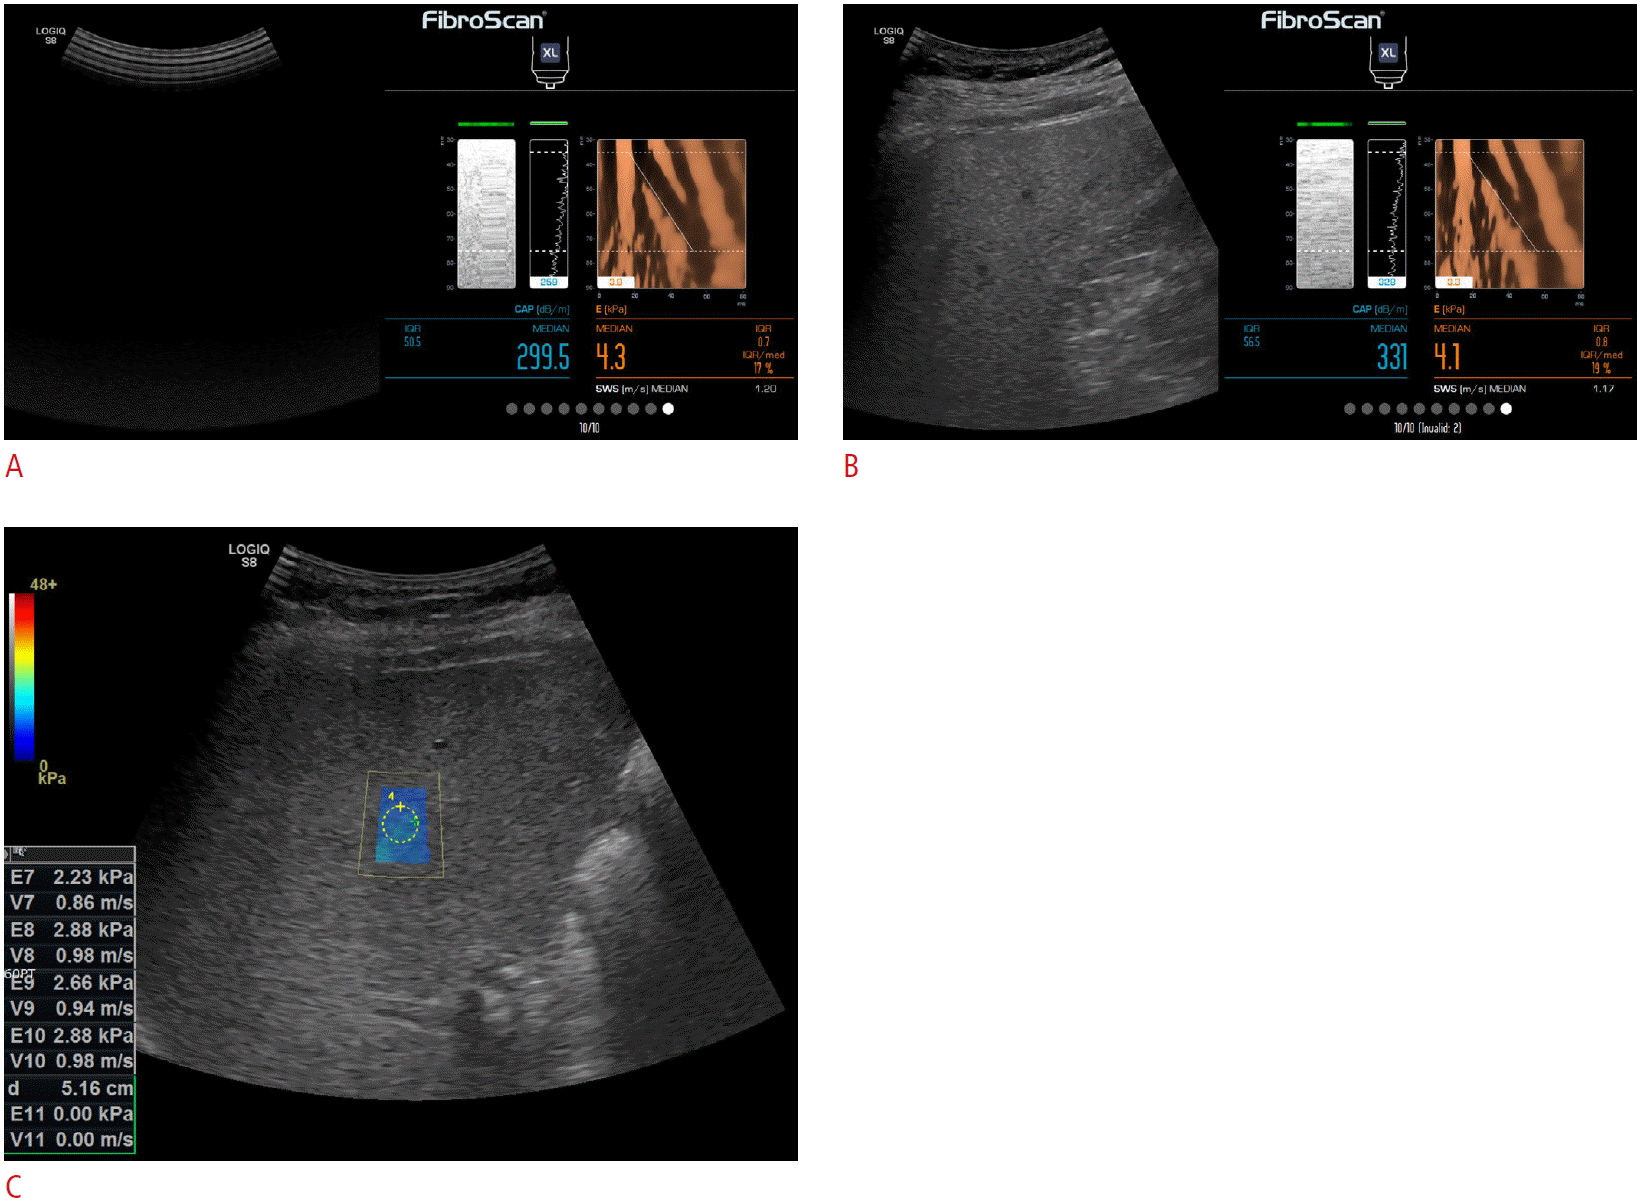

Fig. 1.

LS measurement with conventional TE (A), US-guided TE (B), and 2D-SWE (C).

LS measurement was obtained with TE in two sessions, first in conventional TE (A), and then in US-guided TE (B). In 2D-SWE, LS measurement was obtained from measurement box defined by the operator (C). All LS measurement was obtained using the LOGIQ S8 ultrasound scanner. LS, liver stiffness; TE, transient elastography; US, ultrasound; 2D-SWE, two-dimensional shear wave elastography.

Finally, LS measurements were made with 2D-SWE using the same scanner. 2D-SWE utilizes time-aligned sequential tracking and combpush US shear elastography technology [23,24]. Since an adequate B-mode image is required for LS measurements with 2D-SWE [25], a well-visualized 1×1 cm2 region of interest was established on the right anterior section of the liver using an intercostal approach [26]. This was accomplished by placing the right arm across the sternum (so that the intercostal space was not strained or stretched) while avoiding large vessels and areas with artifacts, approximately 1.5-2.0 cm away from the Glisson capsule (4-5 cm from the transducer) and less than 6 cm deep relative to the capsule. The intention was to avoid reverberation artifacts and areas of increased subcapsular stiffness (Fig. 1).